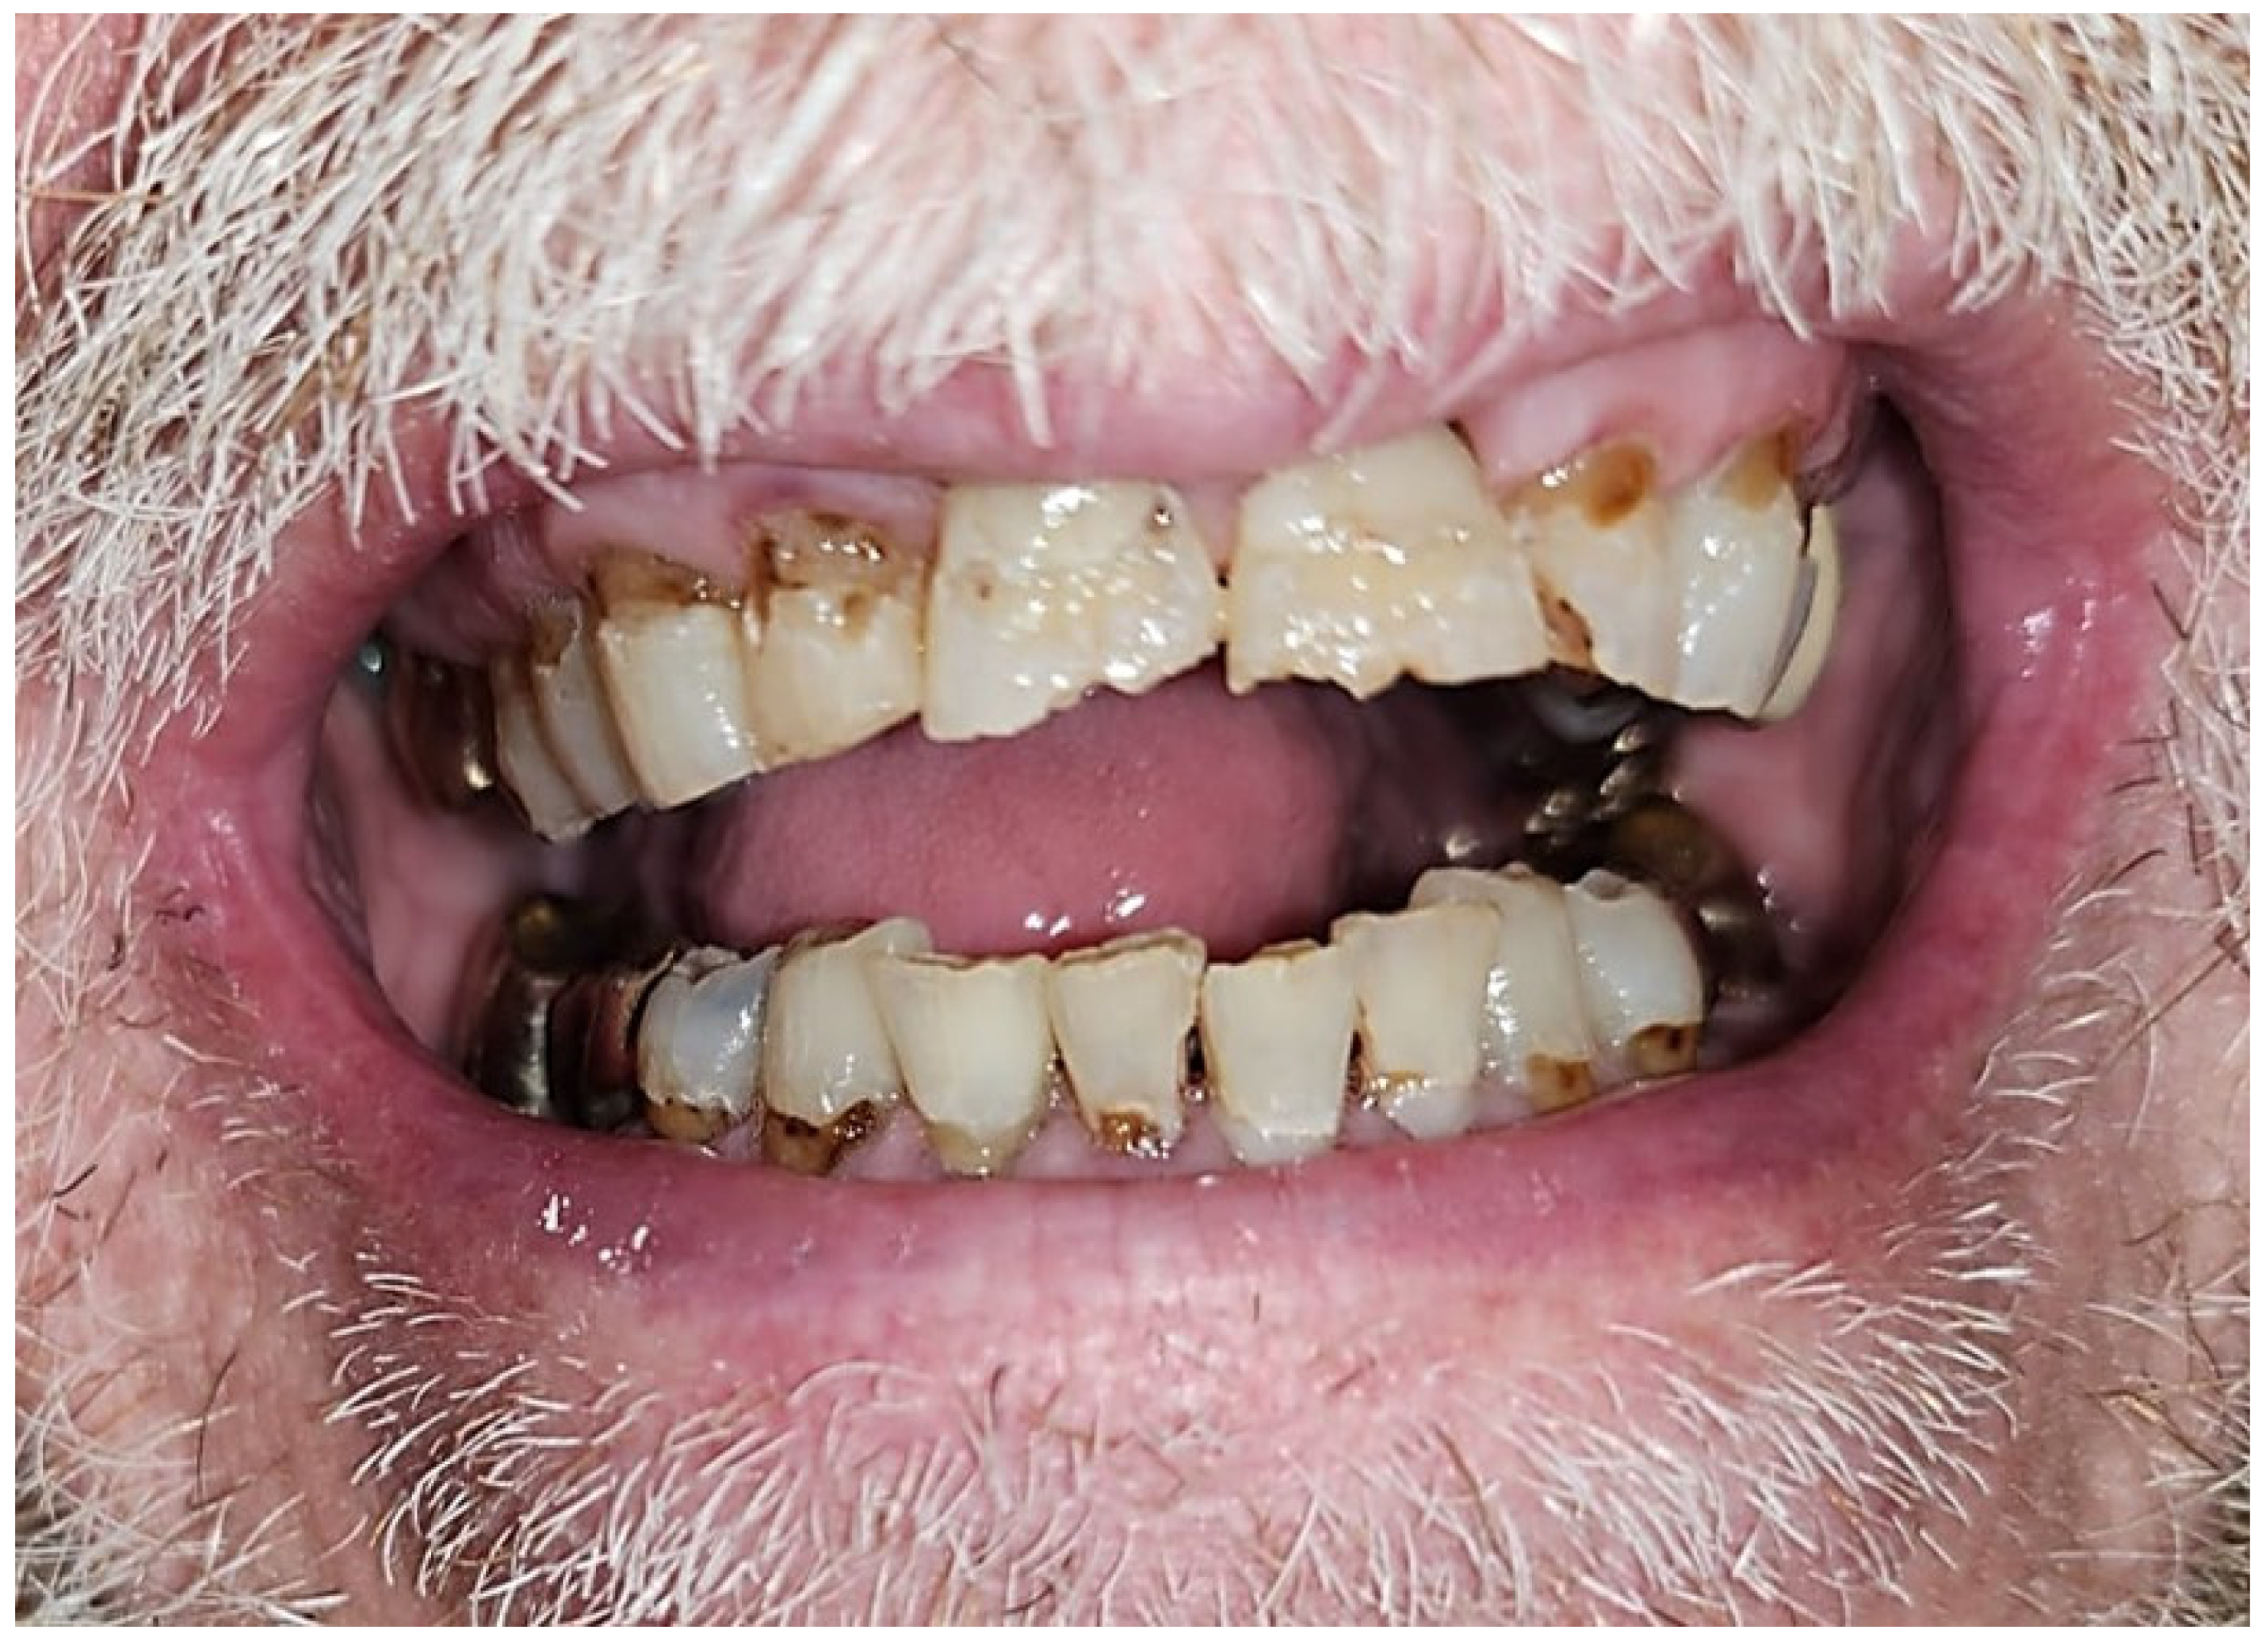

| 1 | M | 69 | Squamous cell carcinoma | Base of Tongue (Oropharynx) | 70 Gy/(Yes) | Mandibular First Molar (#19) | High | Complete Healing |

| 2 | M | 70 | Squamous cell carcinoma | Ventral Tongue/Floor of Mouth (Oral Cavity) [Right] | 70 Gy/(Yes) | Mandibular Incisors and First Molar (#24, #25, #26, and #30) | High | Complete Healing |

| 3 | F | 59 | Squamous cell carcinoma | Tonsil (Oropharynx) [Right] | 70 Gy/(Yes) | Mandibular First Molar (#19) | Moderate | Complete Healing |

| 4 | M | 75 | Adenoid cystic carcinoma | Hard palate/Maxillary Sinus (Oral Cavity) [Left] | 66 Gy/(No) | Mandibular Second Molars (#18 and #31) | Moderate | Complete Healing |